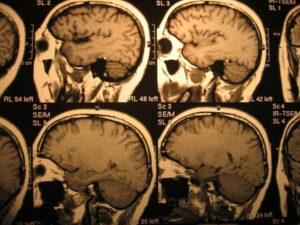

Cerebral palsy is a neurological disorder caused by damage to the developing brain, typically before or during birth. The term “cerebral” refers to the brain, while “palsy” relates to problems with movement and muscle control.

The brain injury does not worsen over time, but the symptoms and physical challenges can change as a child grows and develops. There are several types of cerebral palsy, including:

The severity and symptoms depend on the location and extent of the brain injury.